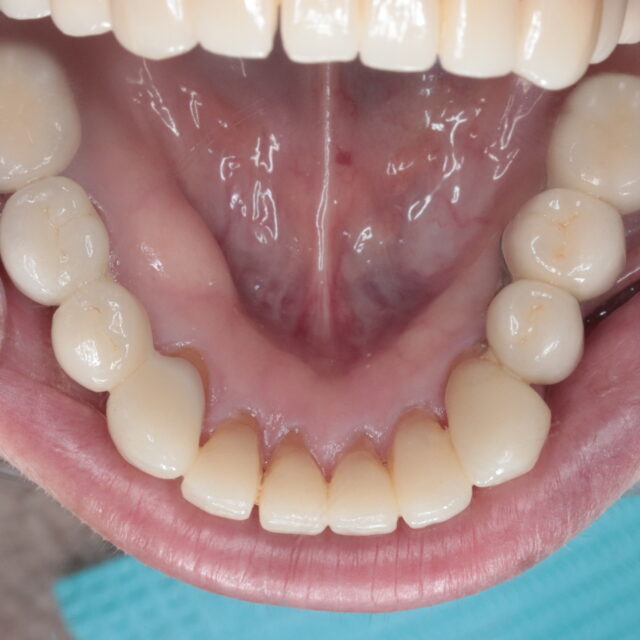

●症例投稿●インプラント治療 03 ~奥歯編~

- 2022年10月16日

- インプラント,咬合治療/フルマウス/咬合再構成